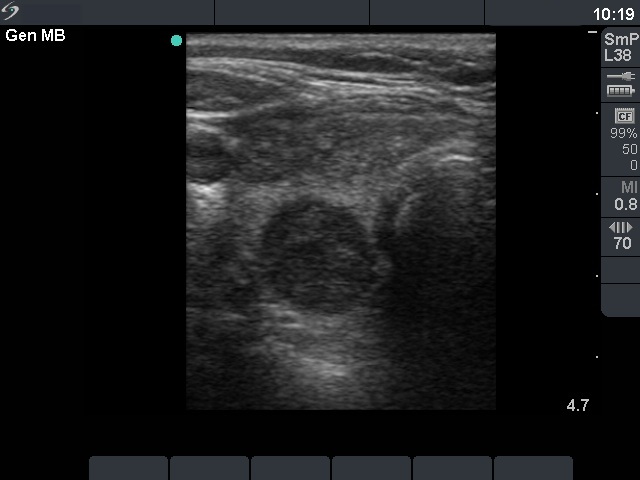

First examination (1st and 2nd rows of images)

Clinical presentation: a 47-year-old woman was referred for evaluation of a multinodular goiter detected on screening. She had no complaints.

Palpation: the right lobe was nodular.

Functional state: euthyroidism with subnormal TSH (TSH 0.18 mIU/L, FT4 18.3 pM/L).

Ultrasonography: the right thyroid contained three nodules, the two ventral lesions were minimally-moderately hypoechogenic, while the dorsal one was hypoechogenic. The latter presented a combined type 2 and type 3 vascular pattern.

Cytology was performed from the dorsal, hypoechogenic nodule and resulted in benign, follicular proliferation. The risk of a carcinoma was estimated to be less than 1%.